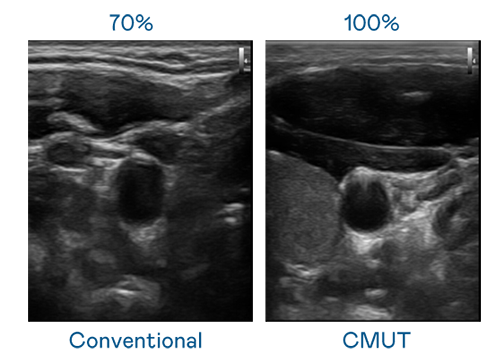

CMUT 技术是一种用电容式微机电元件来产生超音波讯号的技术。与传统 PZT 压电式技术相比,CMUT 频宽增加 30%,更宽频的超音波讯号让影像解析度大幅提升,是实现高影像品质医疗超音波扫描、促进精准医疗发展的关键技术。

大频宽带来超清晰影像

超音波影像的解析度高低,首先取决于探头能发出的讯号频宽。永利娱乐城 CMUT 可提供高清晰的超音波讯号,提供高频宽、高灵敏度、影像纹理细节更高的超音波影像,协助医护人员缩短影像判读时间及利用精准的医疗影像进行诊断。